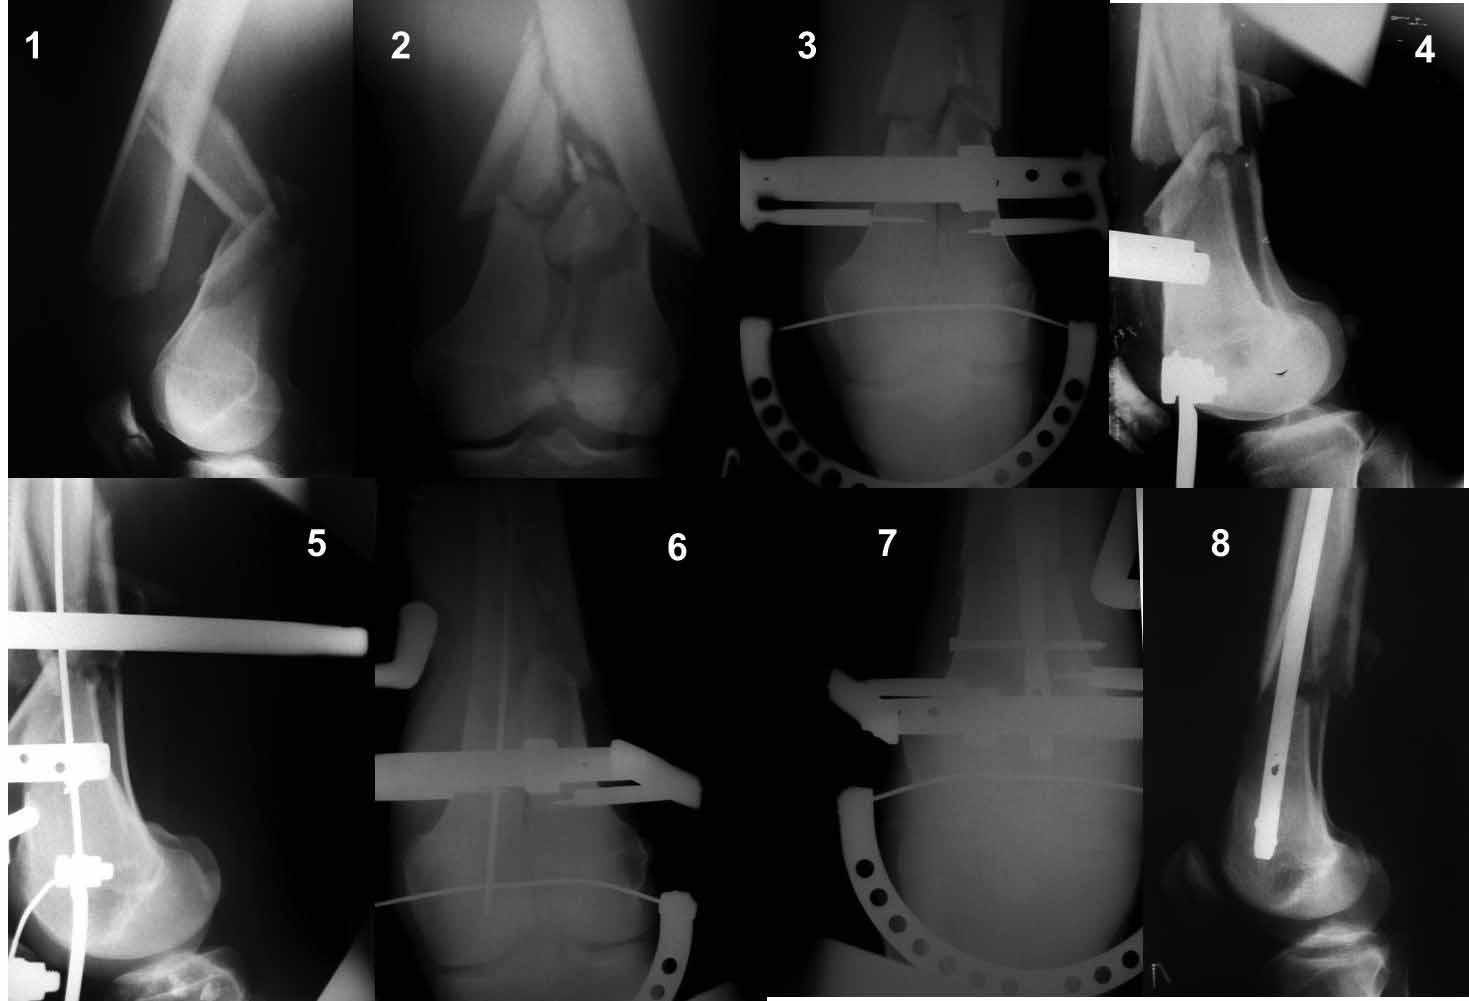

Ну зачем же так. Всё-таки считается "золотым стандартом". Во вложенном файле коллаж из сохранившихся фотографий одной из операций. Всё сделано закрыто и без ЭОПа.

Здесь пример медиальной пластины и латеральный комбинированный метод (у второго больного старый перелом тибиал плато, леченный где то и когда то)

Я не собирался принимать участие в обсуждении данного клинического случая. Считал, что в данном случае всё очевидно. Согласен с Вами, что в данном случае представляется маловероятным закрытым способом выполнить репозицию перелома и что начинать необходимо с открытой репозиции и фиксации медиального мыщелка. После этого оперировать внутрисуставной перелом латерального мыщелка как изолированный (предполагая, что медиальный мыщелок точно и надёжно фиксирован к проксимальному фрагменту), с различными вариантами его фиксации. Целью предыдущего моего поста было желание подчеркнуть возможность закрытой репозиции и фиксации некоторых видов внутрисуставных переломов дистального эпиметафиза бедренной кости методом антеградного блокированного остеосинтеза при которых «любимый» метод становится оптимальным. Согласитесь, что если мыщелки бедренной кости удалось адекватно закрытым способом репонировать и фиксировать между собой, они достаточные по величине для расположения дистальных блокирующих винтов, то такой перелом превращается в банальный перелом бедренной кости с возможностью применения интерлокинга – «золотого стандарта» для диафизарных и метафизарных переломов бедренной кости. И ещё. По многим причинам являюсь «особым энтузиастом» именно антеградного остеосинтеза. Некоторые из них. Оперируем на боку, в custom made репозиционном спицевом аппарате на обычном хирургическом столе. Для определения точки входа используем специальное прицельное устройство, которое устанавливается через проколы кожи на бедренной кости в подвертельной области, позволяющее точно с первого раза в двух плоскостях провести спицу по которой выполняется вскрытие костномозгового канала. Положение больного на боку и применение этого устройства позволяют не учитывать вес и габариты больного. Мы не ищем трохантер или piriformis fossa и в большинстве случаев даже не рассекаем кожу до проведения спицы. Рентген контроль – только для подтверждения расположения спицы.